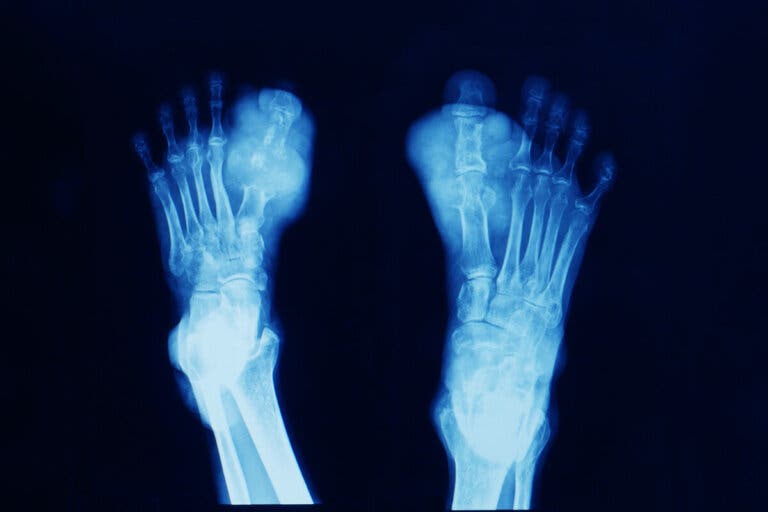

No obstante, si los riñones no funcionan bien o si dicho elemento se produce en cantidades excesivas, este tiende a acumularse en forma de microcristales, ya sea en las articulaciones (gota) o en los riñones (nefrolitiasis). A su vez, eleva el riesgo de enfermedades como el síndrome metabólico, la diabetes y la insuficiencia renal crónica.

La acumulación de cristales de ácido úrico en las articulaciones provoca dolor e inflamación. Por ello, quizá lo último que desee una persona afectada es adoptar una rutina de ejercicio físico. De hecho, cuando se producen los brotes, la recomendación general es descansar y evitar cualquier sobreesfuerzo.